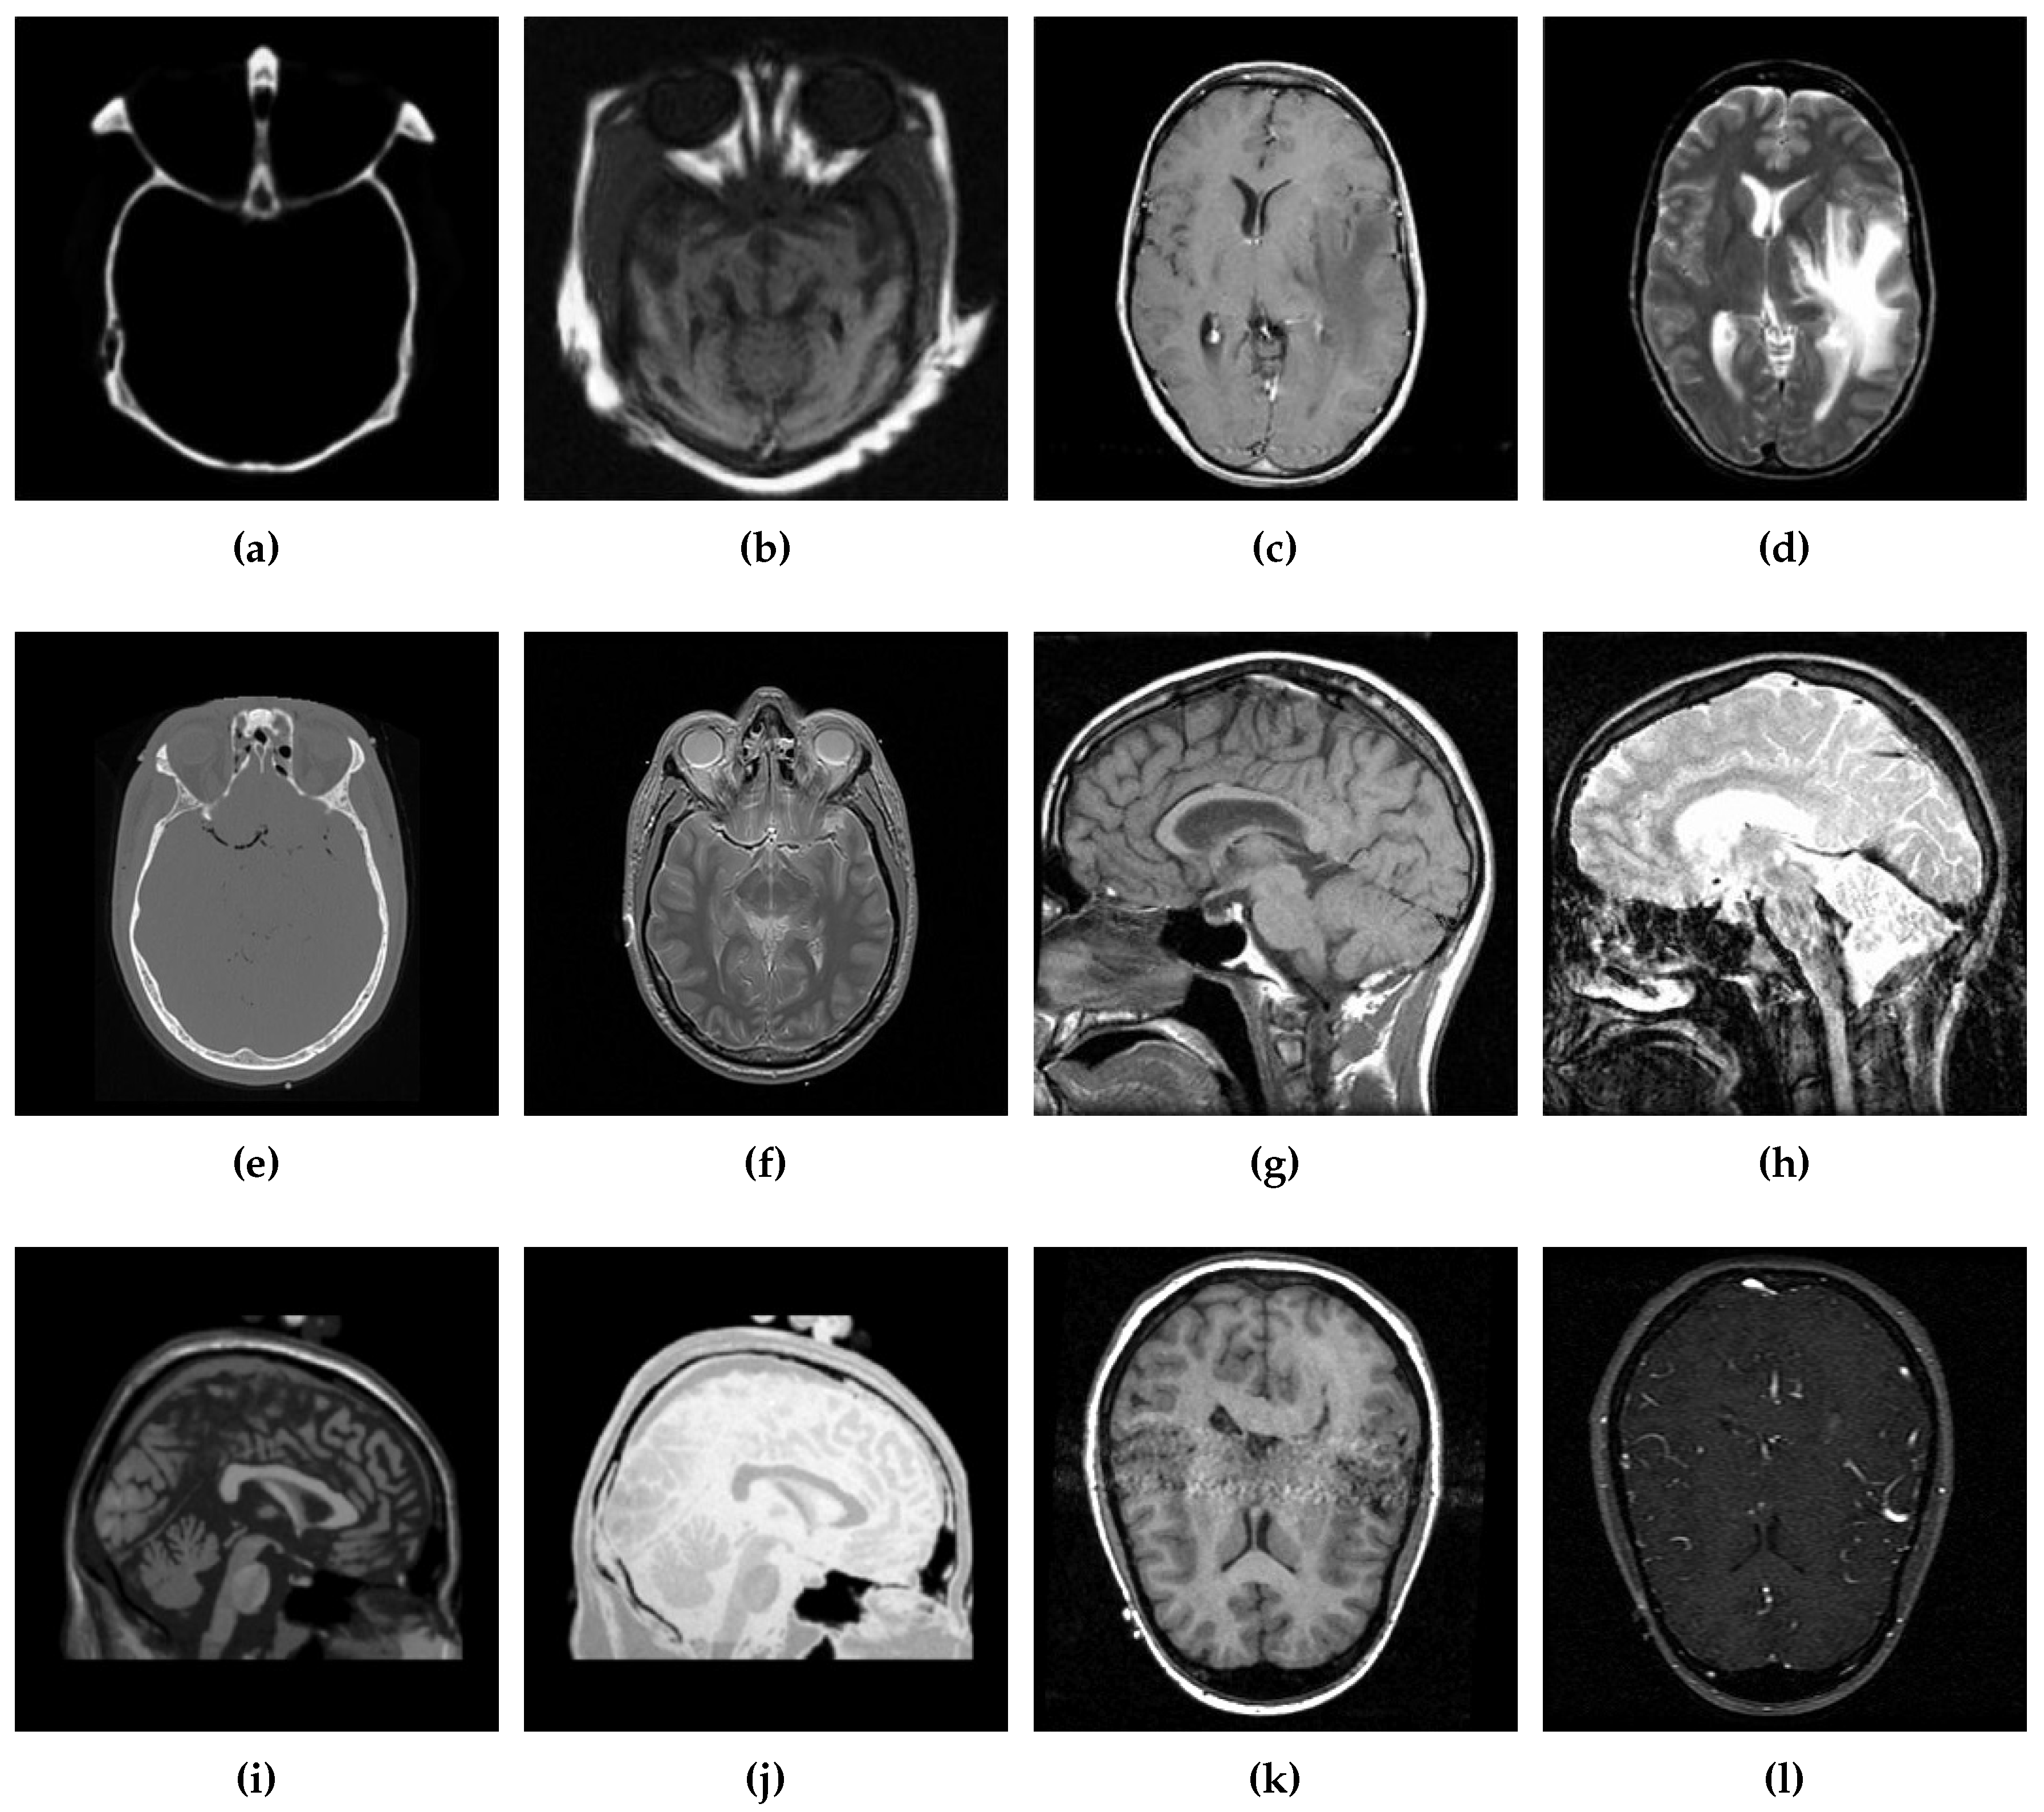

5.2.1. Qualitative Analysis of the Given Set of Algorithms for Multimodal Fusion